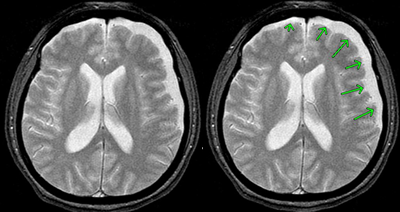

⑨ 慢性硬膜下血腫

慢性硬膜下血腫とは、頭部外傷後慢性期(通常1~2か月後)に、頭蓋骨のすぐ内側で脳を覆っている硬膜と脳との間に血(血腫)が貯まり、血腫が脳を圧迫するものです。

全く異常がなかったのに、だんだん痛みだし、片麻痺、意識障害が徐々に出現・進行してきたり、認知症に似た症状が発生したりします。

高齢の男性に多く、好発部位は前頭、側頭、頭頂部です。右か左かの一側性の血腫が大半です。ときには両側性のこともあります。

頭部打撲をきっかけにして、硬膜と脳との間に少量の出血が起こり、これに脳脊髄液が混ざって血液の量が増えていきます。その反応でつくられる膜から少しずつ出血が繰り返され、血腫が大きくなると考えられています。

受傷直後はわかりにくく一定期間経過後に判明が多い

受傷直後は出血は微量にとどまっていて、CTで確認することはできません。

もっとも、血腫によって脳が圧迫されると症状が出現します。CTで確認できます。

慢性の血腫では血液濃度が薄いときがあり、CTでは灰色や黒色で映ることもあります。もちろん、MRIも診断に有用です。

外傷後、無症状の期間を経て、3週間~数か月以内に発症します。